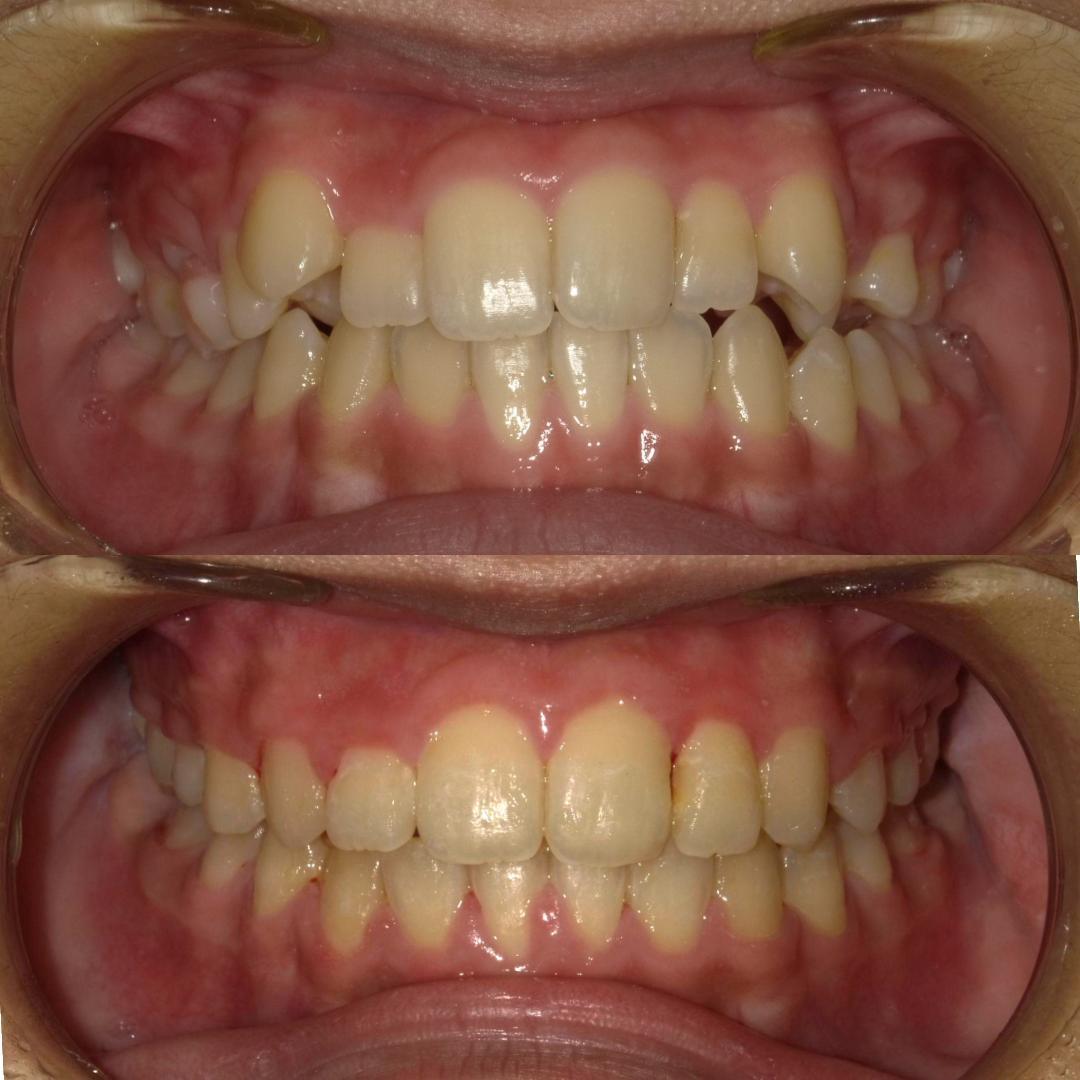

そういった様々な要因を取り除くことで、従来、小臼歯(4番、5番)を抜歯しなければ治療できない症例でも、非抜歯で治療可能となってきているのです。

機能的に小臼歯は非常に大切な歯であることから、最大限小臼歯を抜歯せずに治療できる治療方針を考えます。

また、下顎の位置関係、歯の傾きなどの原因を新素材ゴムメタルワイヤーで治療を行うことでほとんどの症例で小臼歯を抜歯しなくても治療可能になってきています。